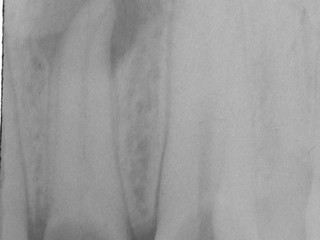

Quello che il dentista può vedere, attraverso un esame radiografico, è una “lesione periapicale”, cioè una zona di osso meno calcificato (e quindi più trasparente ai raggi X) situata intorno alla punta della radice.

Se noi riusciamo a rimuovere l’infezione (detergendo e sigillando correttamente i canali radicolari infetti) questa lesione guarisce nel giro di pochi mesi.

A questo punto inizia il processo di guarigione che, nei controlli successivi, consentirà di verificare (in una alta percentuale di casi) che l’osso si è riformato e il granuloma è sparito.